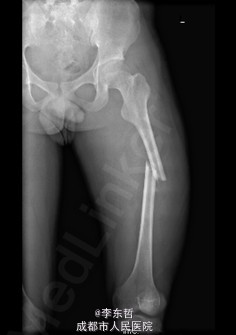

患者男,19岁,因“车祸伤致左下肢活动障碍5小时”入院。5小时前,患者骑电瓶车不慎与另一电动摩托车相撞倒地,当即感左大腿疼痛,畸形,活动受限,右小腿皮肤挫伤、出血,无头晕头痛,无大小便失禁。就诊于当地医院,检查提示:左股骨中段横行骨折。急诊行左大腿夹板外固定,右小腿清创缝合术,术后未进一步治疗,患者为进一步诊治来我院,急诊以左股骨中段骨折收入我科。 自患病以来,患者一般情况尚可,精神睡眠可,小便正常,大便未解。

查体:左大腿夹板固定,肿胀明显,短缩、畸形,右小腿内前方可见一长约5cm创口,已缝合,内植引流条一根,无明显肿胀。左大腿中段环周压痛,可扪及骨折断端,右小腿无明显压痛,双下肢感觉正常。左膝及髋关节明显活动受限,左足背及右下肢活动正常。 辅查:外院X片示:左侧股骨中上段可见骨质断裂征象,断端分离、错位、重叠,周围软组织肿胀;双侧胫腓骨、左膝关节各骨及左踝关节未见确切骨质断裂征象。

初步诊断:1、左股骨中段横行骨折,2、右小腿皮肤软组织裂伤清创缝合术后。 诊疗计划:1、向患者及家属交待病情及注意事项。2、向上级医生汇报患者病情。3、完善术前相关检查。4、给予皮肤牵引、抬高患肢等对症处理。5、拟进一步手术治疗。6、密切观察病情变化,根据病情及时处理